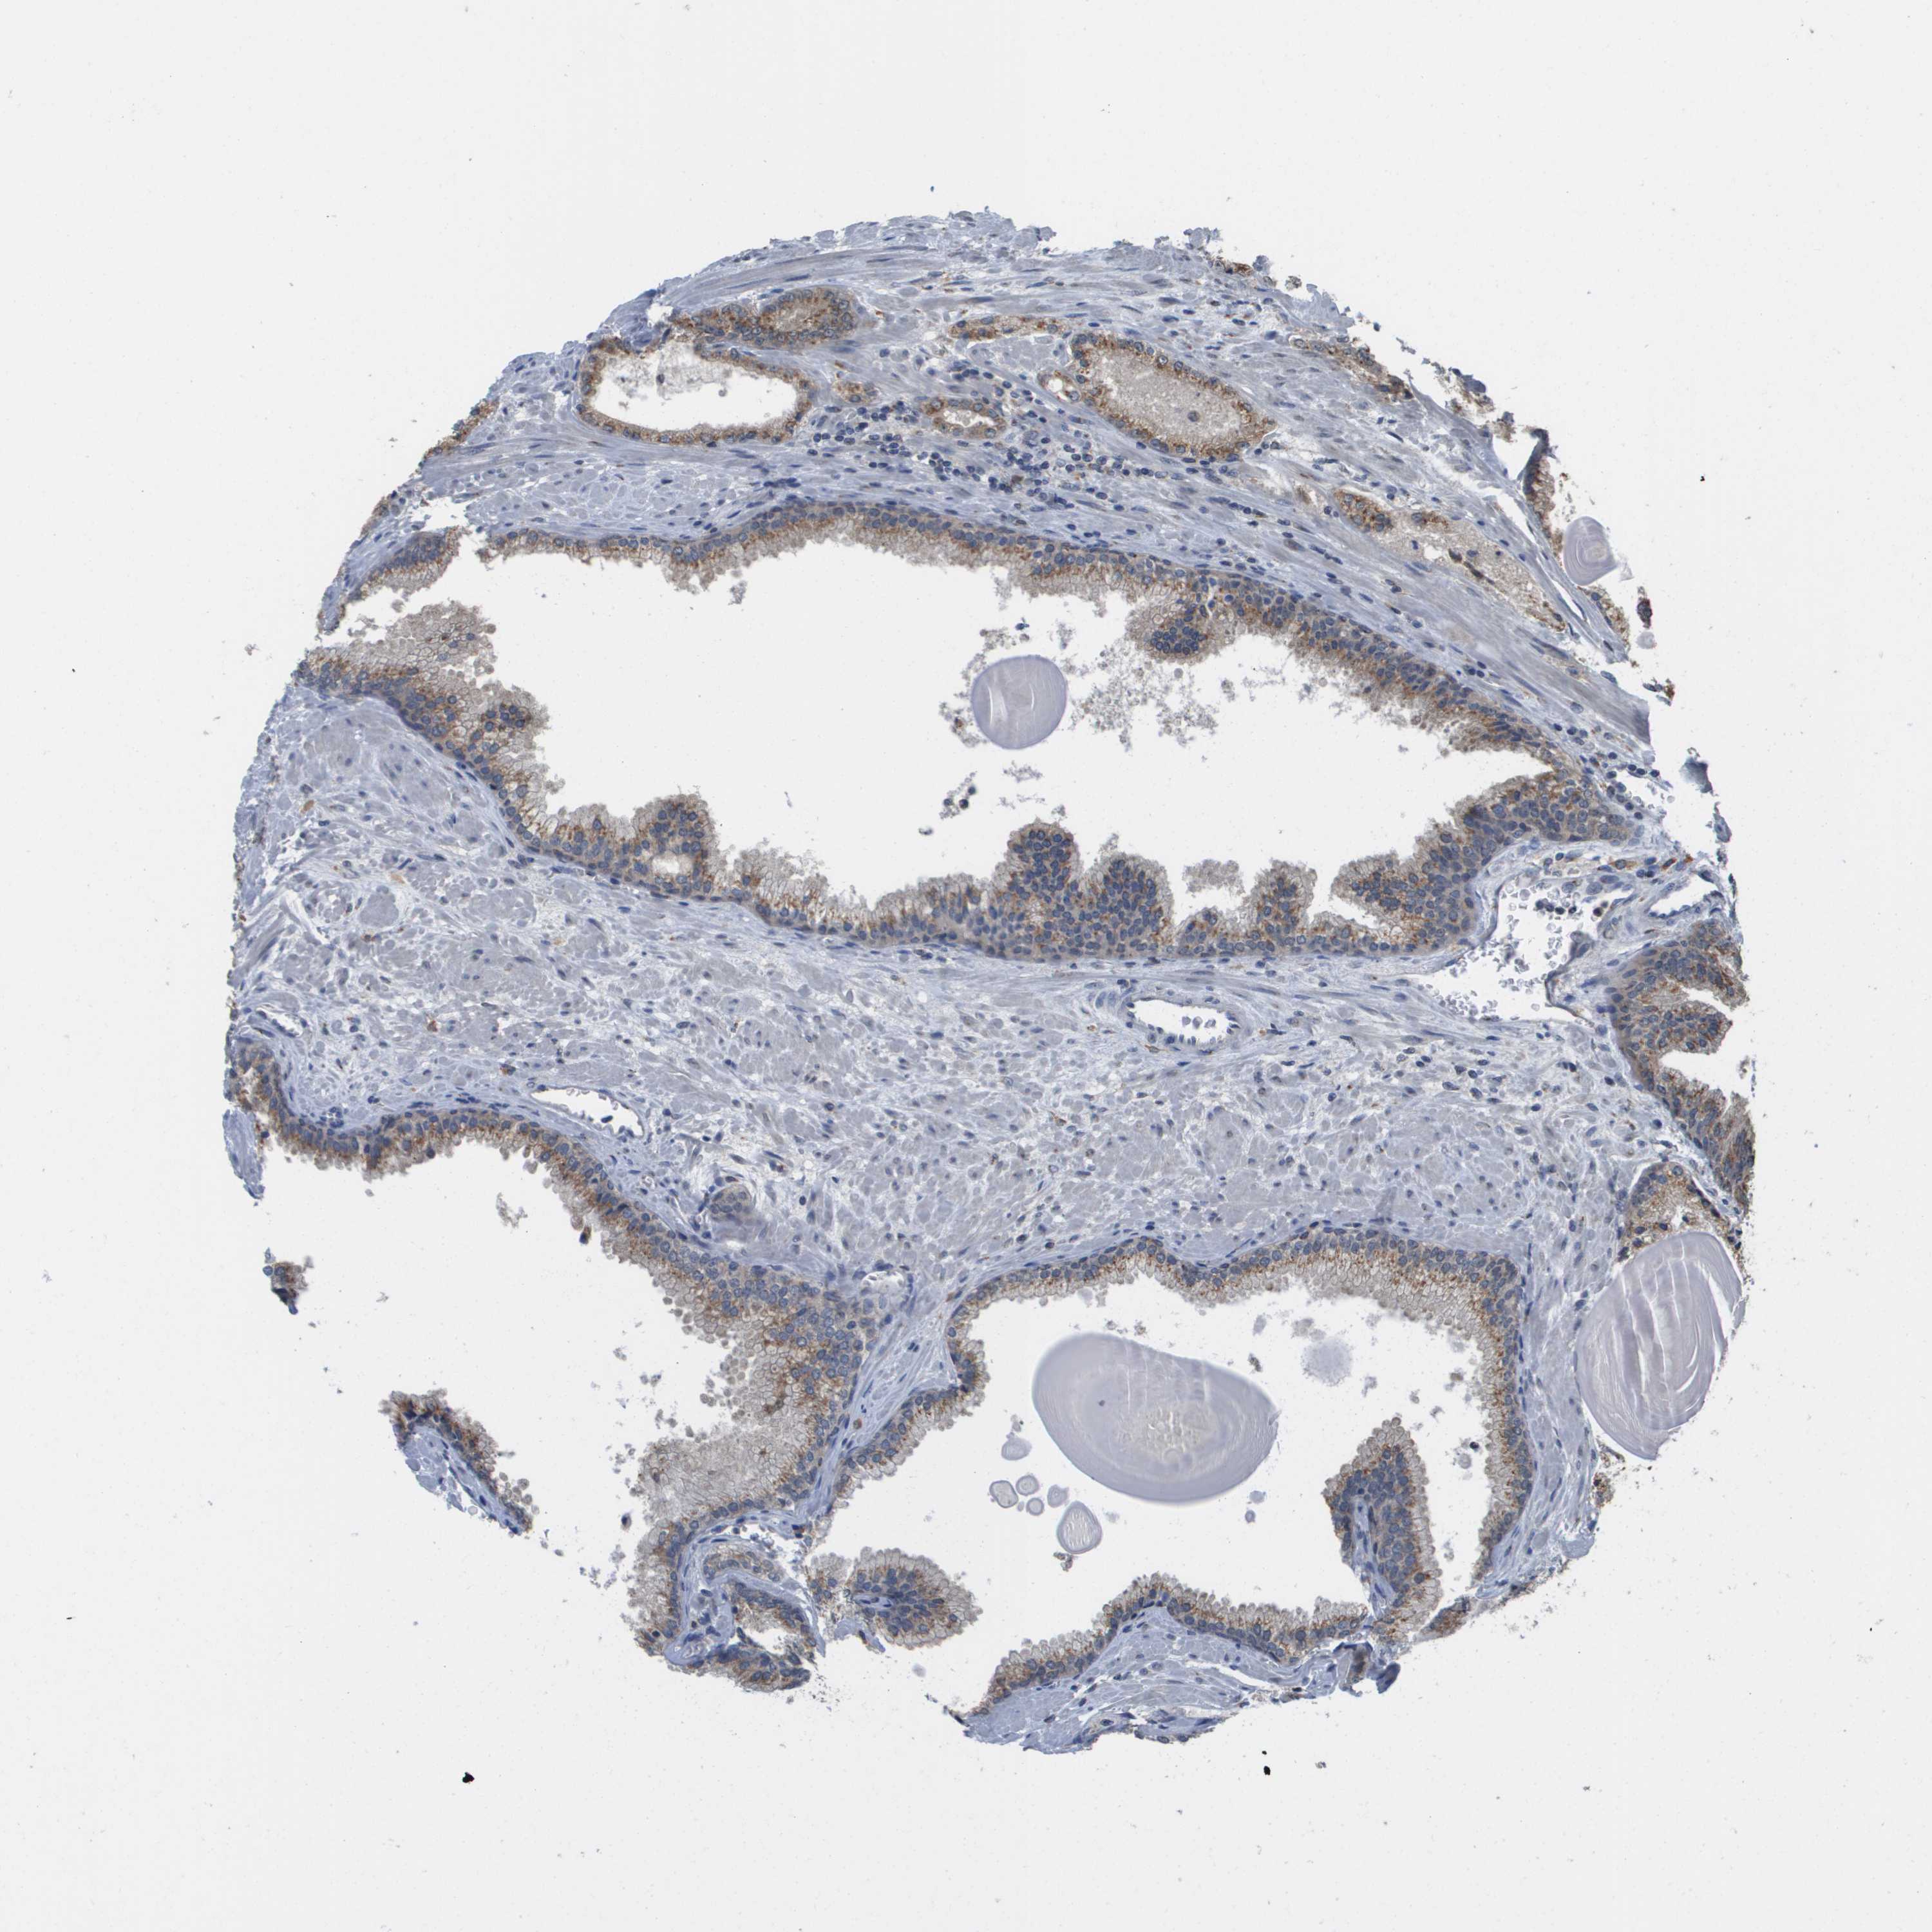

PROSTATE CANCER - Protein expressioni

A mouse-over function shows sample information and annotation data. Click on an image to view it in a full screen mode. Samples can be filtered based on level of antibody staining by selecting one or several of the following categories: high, medium, low and not detected. The assay and annotation is described here.

Antibody stainingi

Antibody staining in the annotated cell types in the current human tissue is reported as not detected, low, medium, or high, based on conventional immunohistochemistry profiling in selected tissues. This score is based on the combination of the staining intensity and fraction of stained cells.

Each image is clickable and will lead to virtual microscopy that enables deeper exploration of all samples and also displays staining intensity scores, fraction scores and subcellular localization as well as patient and tissue information for each sample.

Antibody HPA006277

Antibody HPA006507

Antibody CAB017027

Staining

High

Medium

Low

Not detected

Intensity

Strong

Moderate

Weak

Negative

Quantity

>75%

75%-25%

<25%

None

Location

Nuclear

Cytoplasmic/membranous

Cytoplasmic/membranous,nuclear

Adenocarcinoma, High grade

Adenocarcinoma, Low grade